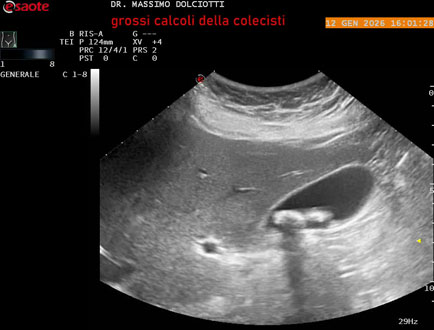

Data inserimento: 25/08/2025

Ecografia del: 08/08/2025

Strumento: Esaote MyLab Eight

Sonda: Convex Multifrequenza 1-8 MHz

Età Paziente: F 52 anni

Motivazione dell'esame: dolore all'ipocondrio destro

Commento all'esame: le immagini ed il video documentano immagine iperecogena delle dimensioni di 21 mm, con cono d'ombra posteriore, da ricondurre a grosso calcolo delle colecisti.

Conclusioni: grande calcolo della colecisti (large gallstone).

Presentazione: Dr. Massimo Dolciotti - Ancona

Elaborazione digitale: Andrea Dini - Ancona